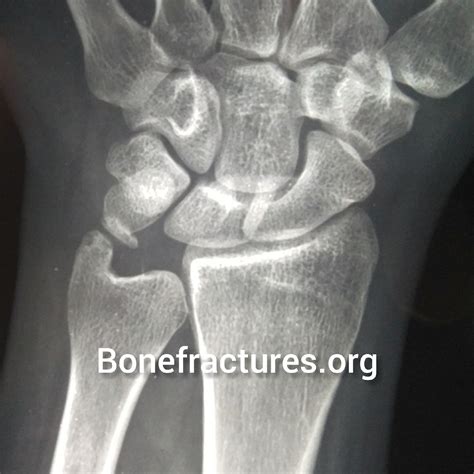

At its core, Ulnar Impaction Syndrome is a degenerative condition characterized by the mechanical abutment of the distal ulna—the bone on the pinky side of your forearm—against the bones in the wrist (specifically the lunate and triquetrum) and the triangular fibrocartilage complex (TFCC). In a healthy wrist, the radius and ulna work in harmony to support the carpal bones. However, if the ulna is relatively longer than the radius, a condition called “ulna positive variance,” it creates a crowded space that leads to repetitive grinding, cartilage wear, and ligament tears.

Imaging is equally vital. Standard X-rays, particularly those taken in a neutral position, help clinicians measure the ulnar variance. In more complex cases, an MRI is ordered to evaluate the extent of TFCC damage, cartilage wear on the lunate, or subchondral bone edema, which is the "bruising" of the bone caused by persistent impaction.